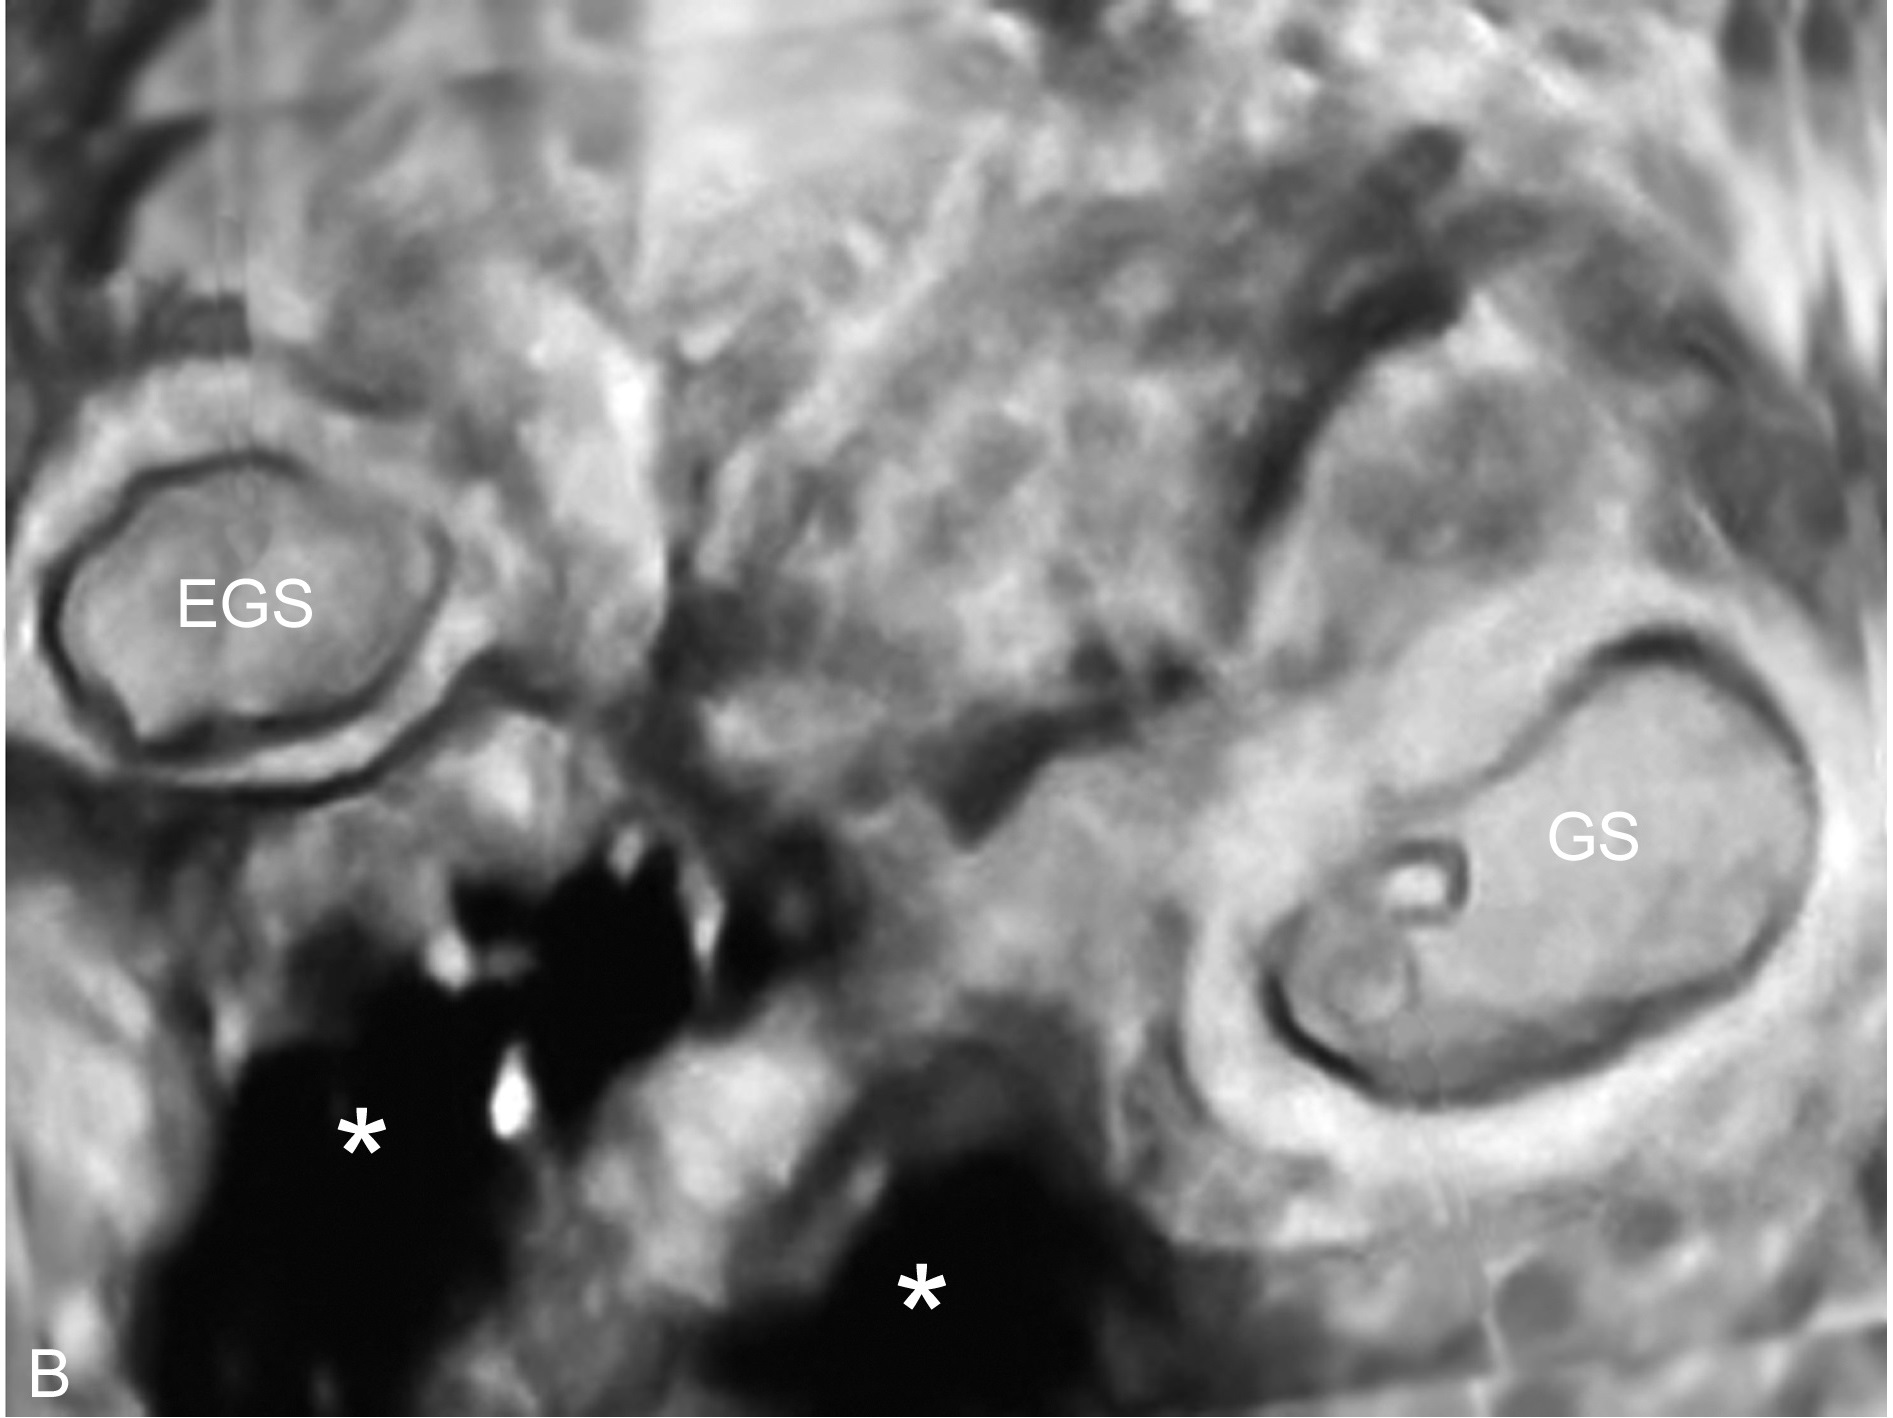

2、宫外孕与宫腔内妊娠合并发生:在自然妊娠中,宫外孕与宫腔内妊娠合并发生率为1:30000。故一般认为显示了宫内妊娠即可排除宫外妊娠,但随着辅助生殖技术及促排卵药物的应用其发生率明显增加。临床诊断困难。如果子宫腔内有妊娠囊显示,同时也显示了宫外妊娠的征象(图1,2),亦应作出宫腔内外同时妊娠的诊断。

图2 三维重建:宫内妊娠(GS)合并宫外孕(EGS)腹腔积血(*)